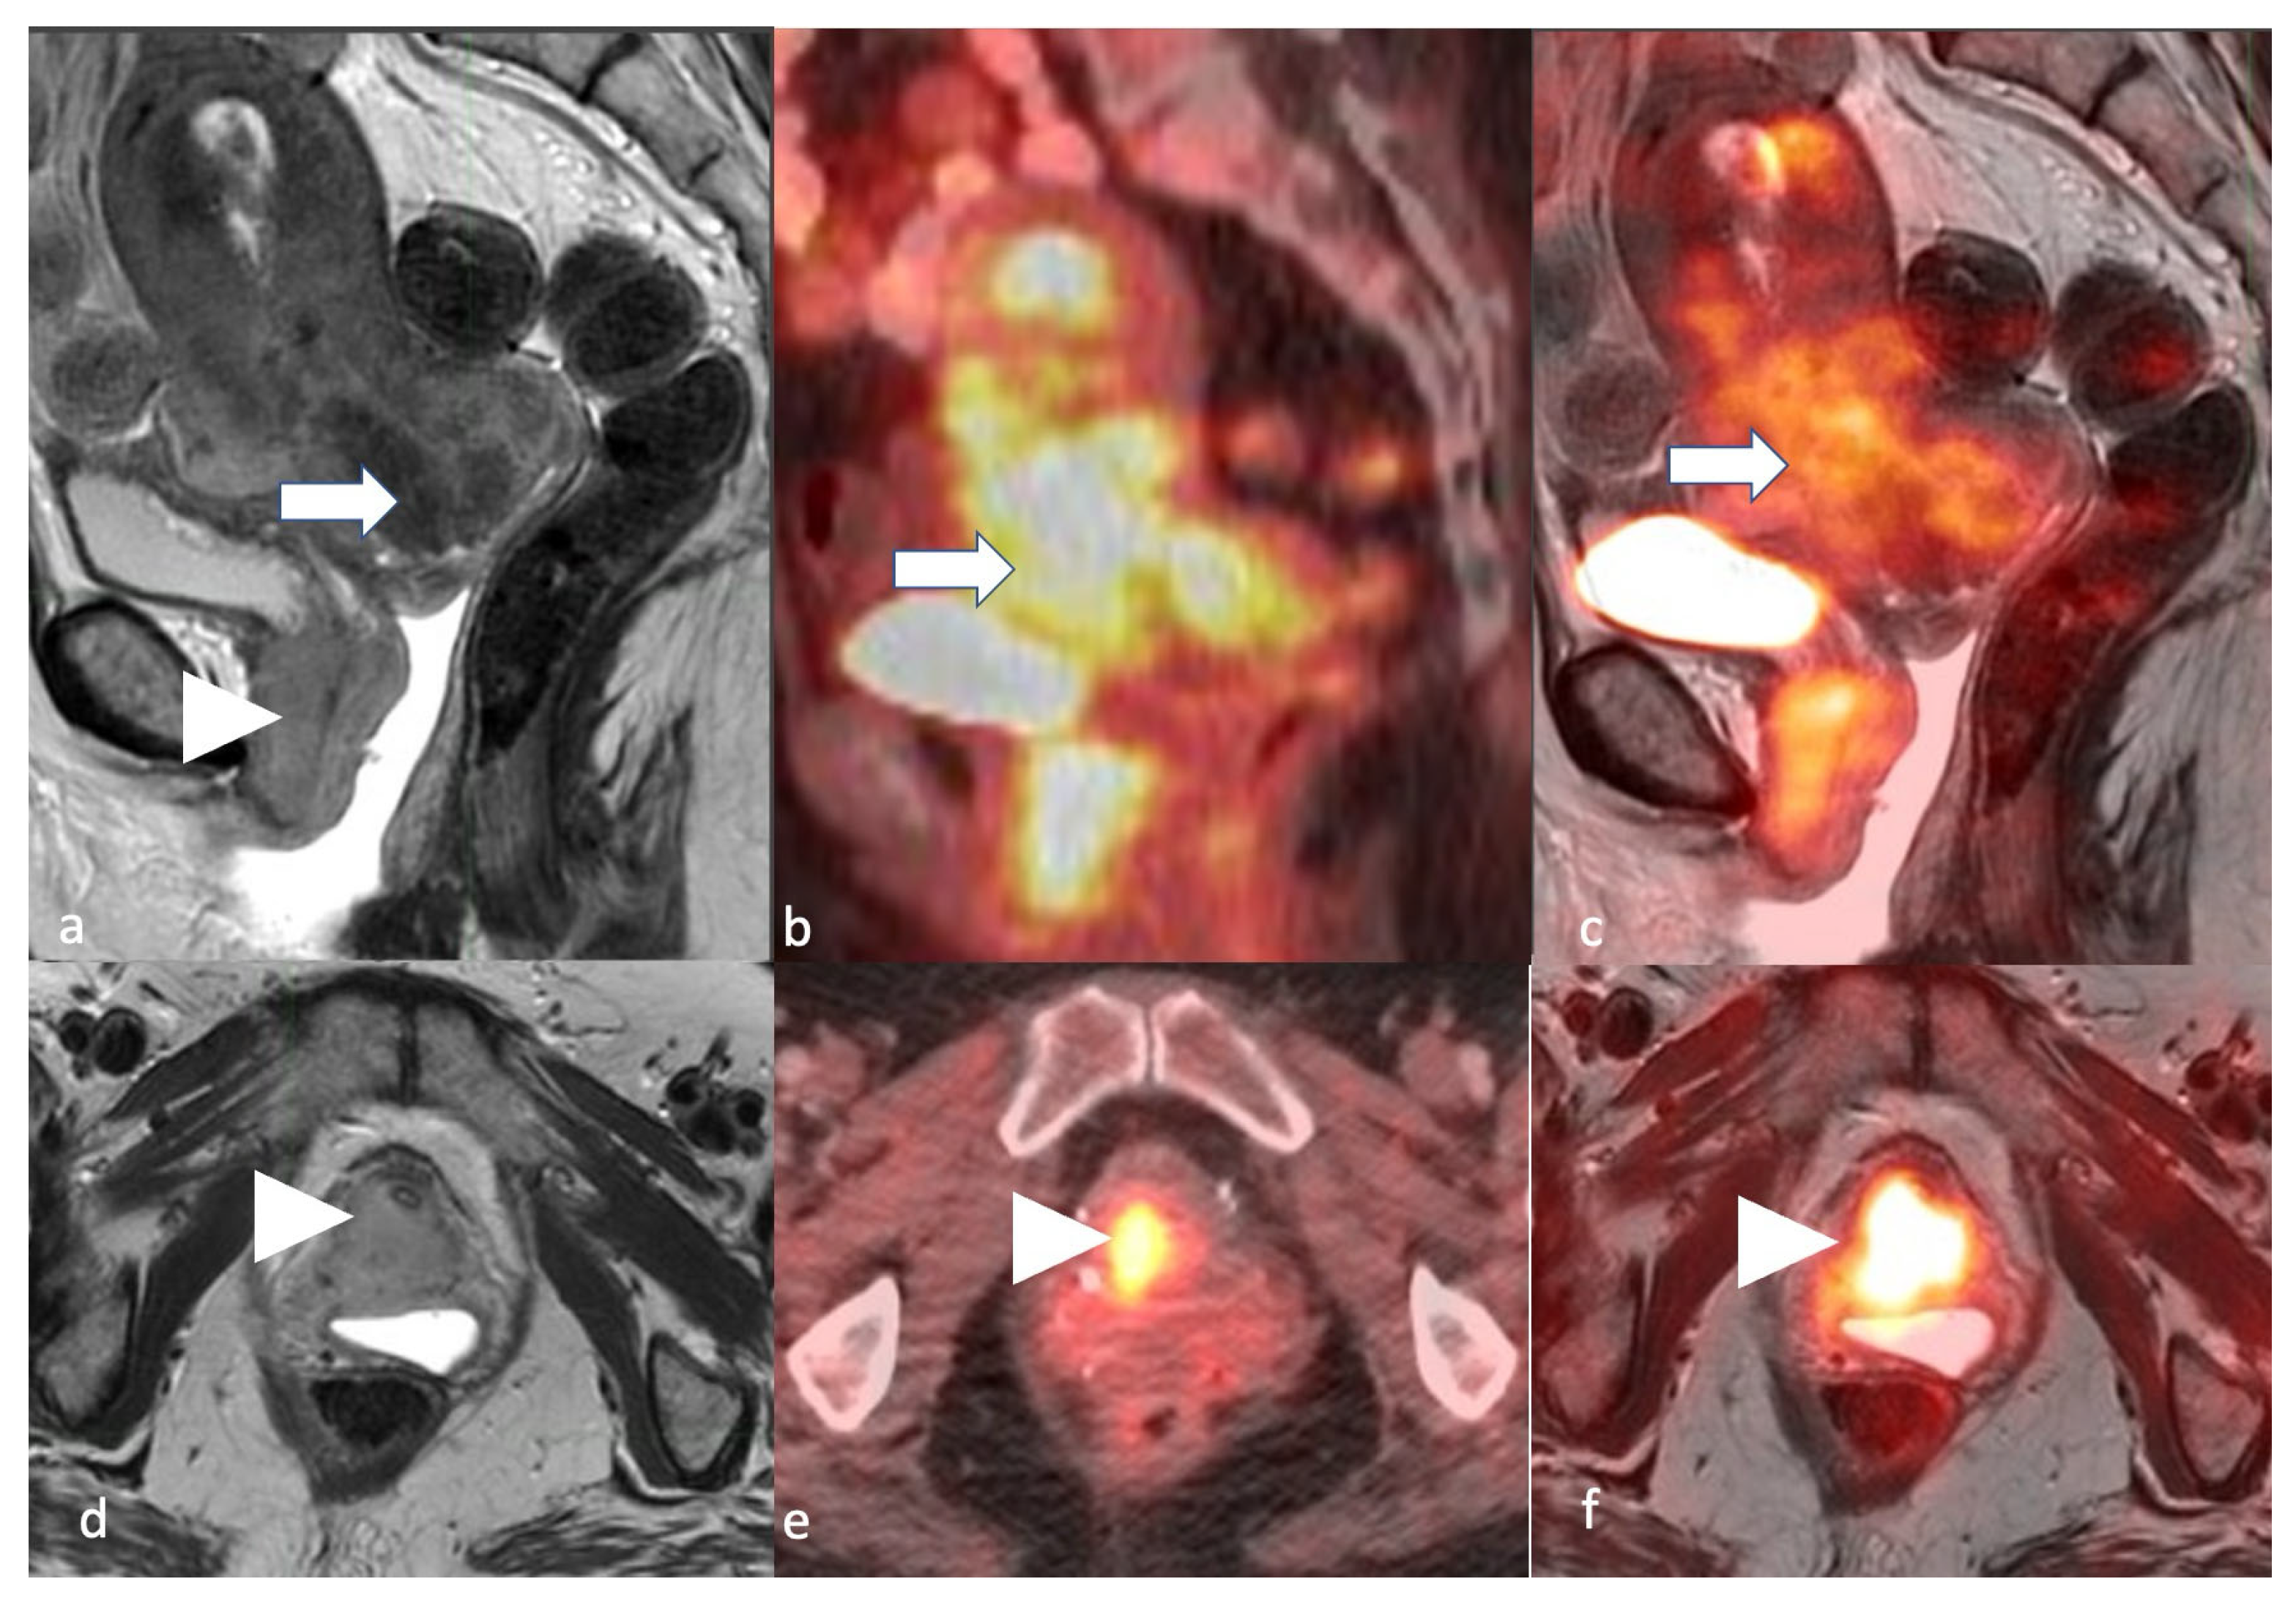

5.4. Positron Emission Tomography/Computed Tomography (PET/CT)

5.5. Positron Emission Tomography/Magnetic Resonance Imaging (PET/MRI)

- Fasmer, K.E.; Gulati, A.; Dybvik, J.A.; Wagner-Larsen, K.S.; Lura, N.; Salvesen, Ø.; Forsse, D.; Trovik, J.; Pijnenborg, J.M.A.; Krakstad, C.; et al. Preoperative pelvic MRI and 2-[(18)F]FDG PET/CT for lymph node staging and prognostication in endometrial cancer-time to revisit current imaging guidelines? Eur. Radiol. 2023, 33, 221–232. [Google Scholar] [CrossRef]

- Tsuyoshi, H.; Tsujikawa, T.; Yamada, S.; Okazawa, H.; Yoshida, Y. Diagnostic value of (18)F-FDG PET/MRI for staging in patients with endometrial cancer. Cancer Imaging 2020, 20, 75. [Google Scholar] [CrossRef] [PubMed]

- Ironi, G.; Mapelli, P.; Bergamini, A.; Fallanca, F.; Candotti, G.; Gnasso, C.; Taccagni, G.L.; Sant’Angelo, M.; Scifo, P.; Bezzi, C.; et al. Hybrid PET/MRI in Staging Endometrial Cancer: Diagnostic and Predictive Value in a Prospective Cohort. Clin. Nucl. Med. 2022, 47, e221–e229. [Google Scholar] [CrossRef] [PubMed]

- Jónsdóttir, B.; Ripoll, M.A.; Bergman, A.; Silins, I.; Poromaa, I.S.; Ahlström, H.; Stålberg, K. Validation of 18F-FDG PET/MRI and diffusion-weighted MRI for estimating the extent of peritoneal carcinomatosis in ovarian and endometrial cancer—A pilot study. Cancer Imaging 2021, 21, 34. [Google Scholar] [CrossRef] [PubMed]